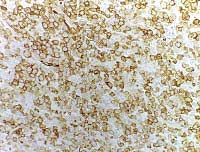

![]()

ENLARGE

and

EMA antigens